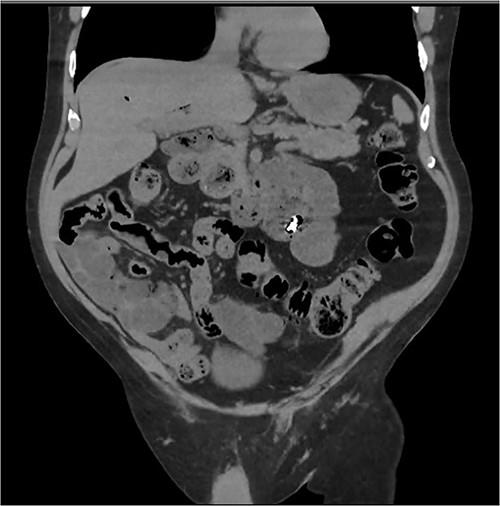

Abdominal CT identifying one hearing aid in a jejunal diverticulum 3 weeks after initial presentation – axial view.

Abdominal CT identifying one hearing aid in a jejunal diverticulum 3 weeks after initial presentation – coronal view.